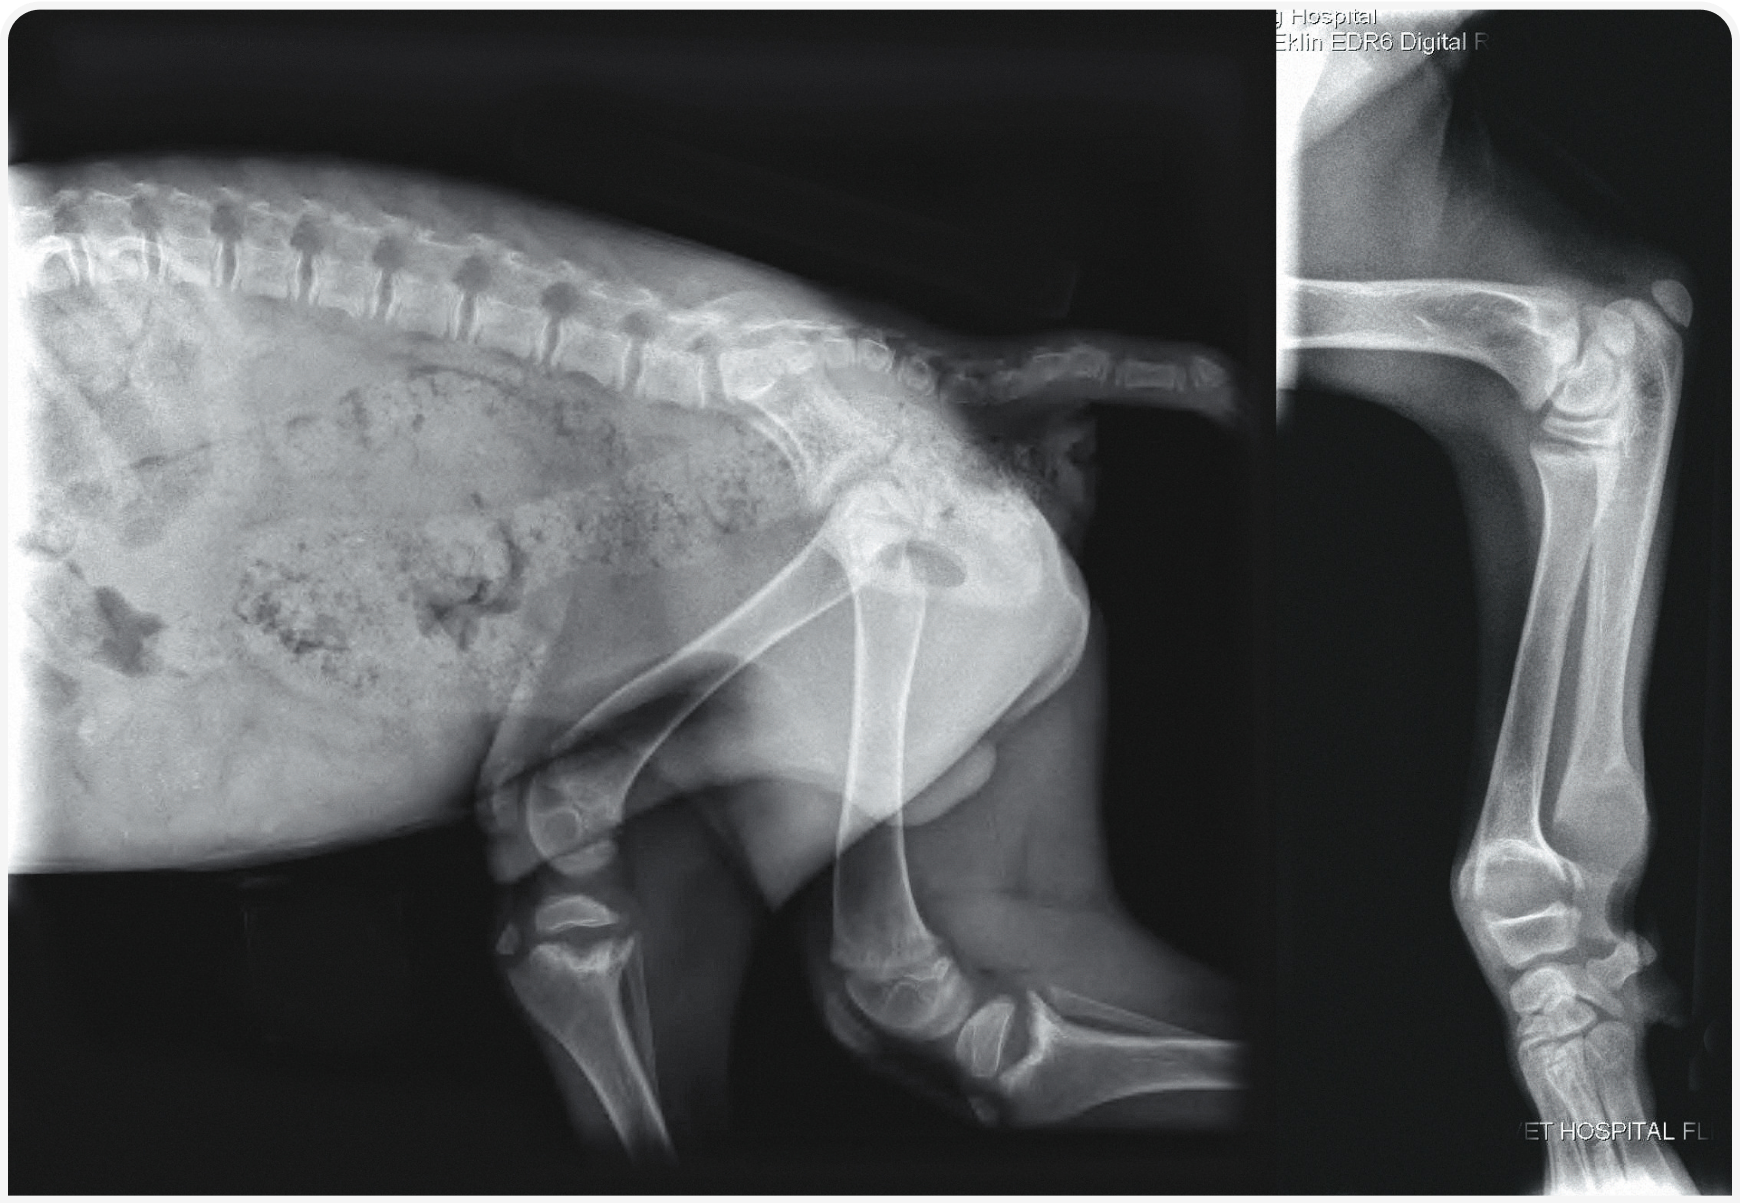

18. Johnson KA, Church DB, Barton RJ, et al. Vitamin D-dependent rickets in a Saint Bernard dog. J Small Anim Pract 1988;29:657-666.

19. LeVine DN, Zhou Y, Ghiloni RJ, et al. Hereditary 1,25-dihydroxyvitamin D- resistant rickets in a Pomeranian dog caused by a novel mutation in the vitamin D receptor gene. J Vet Intern Med 2009;23:1278-1283.